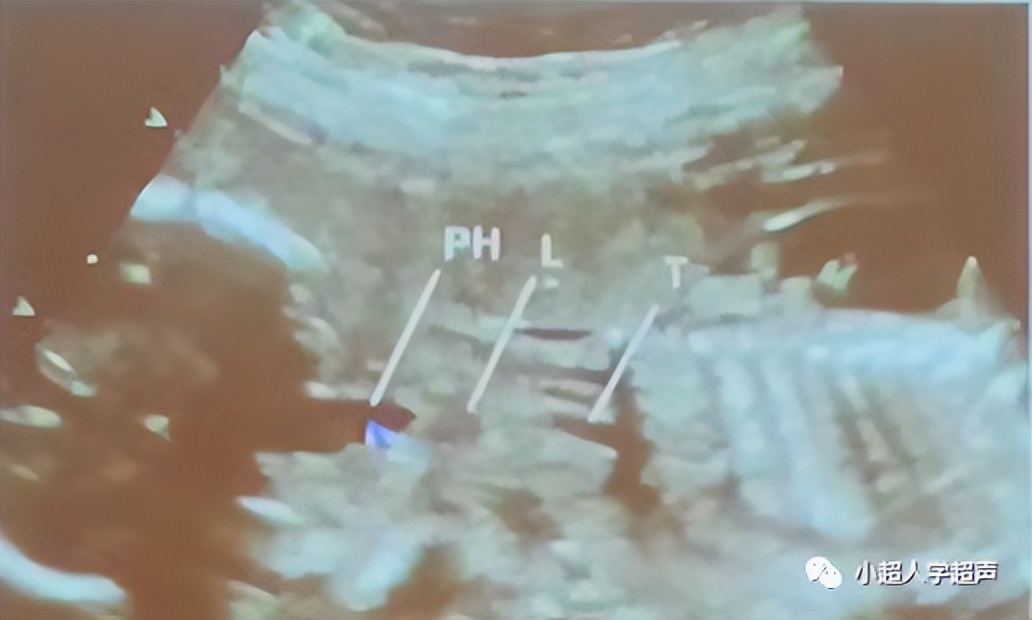

超声表现为四条线状高回声,代表食道的前后壁。食道内因胎儿吞咽偶尔可见液体,因而可显示为一根细小的管道。

由于食道并不成一条直线,多数情况下显示整体结构比较困难。颈部、胸部和腹部部分可分别显示。

- 颈段食道在矢状面显示最佳

- 胸段则在气管后面,与气管平行

- 最远端的腹部部分偏离脊柱,在胃的入口处可以看见。

- 在早孕期(12--16周)采用经阴道探头观察食道比晚孕期容易

- 晚孕期则可用高分辨线性探头观察